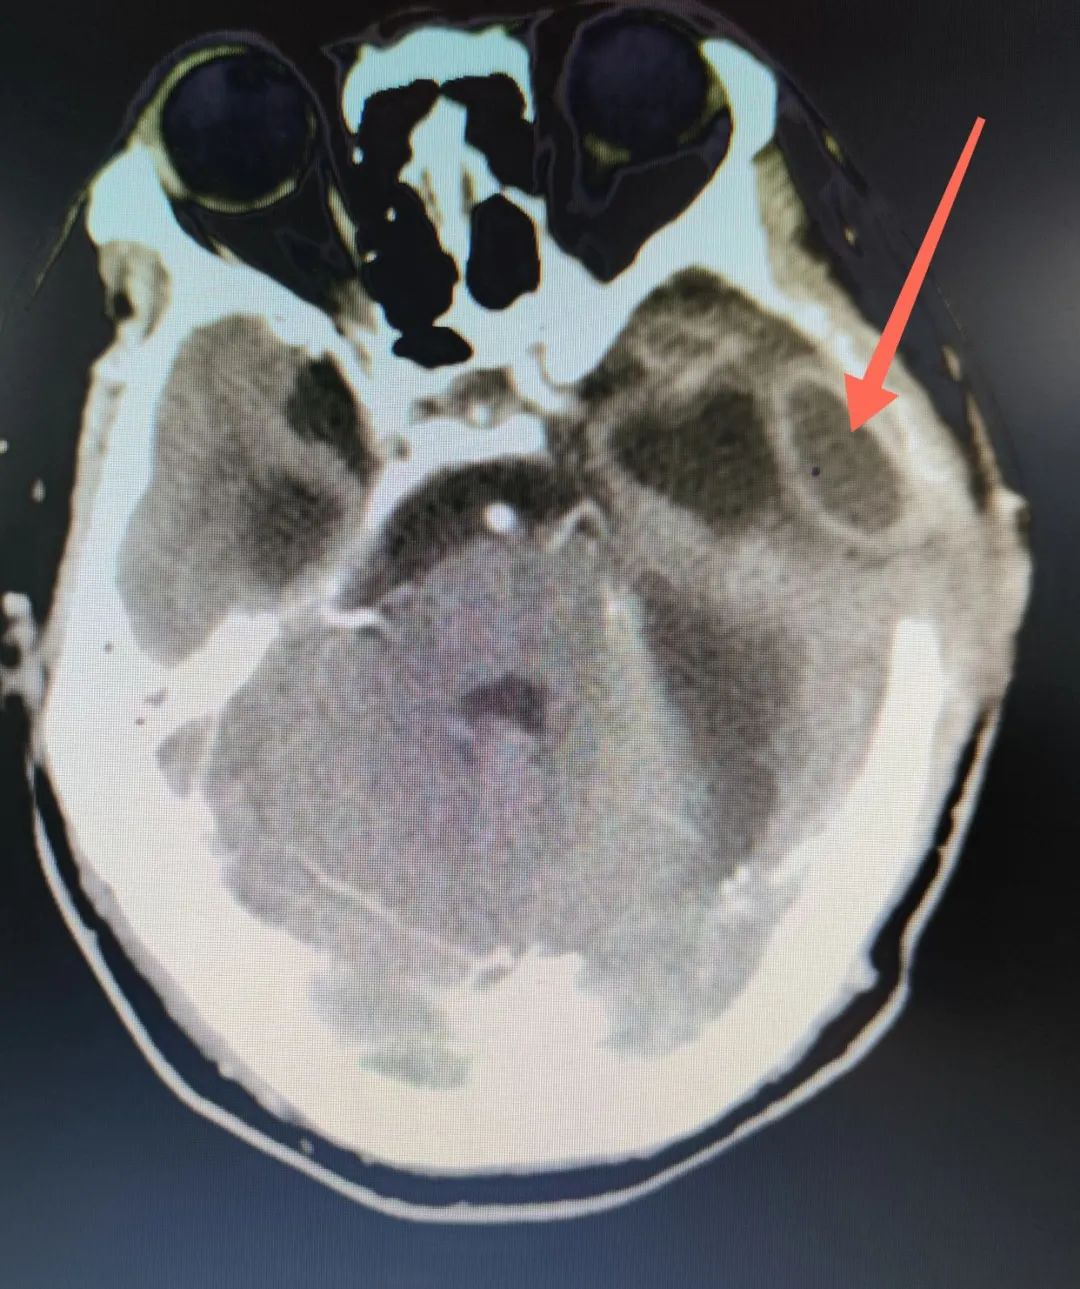

CT增强可见左侧侧脑室颞角旁、减压窗骨缘前脓肿形成,紧邻脑室。

术前增强CT可见脑室扩张,减压窗脑膨出明显。